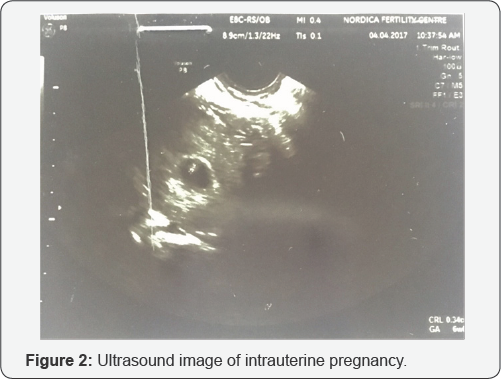

She had a similar antagonist protocol but this time the starting dose of FSH was 450IU. She produced 6 follicles from which 6 eggs were retrieved however only 3 were metaphase II eggs. Two of this fertilized following ICSI and two Day 3 embryos were smoothly transferred under abdominal ultrasound guidance into her uterine cavity placing them about 2cm short of the uterine fundus. She had a pregnancy test after an uneventful 2 week wait which was positive. An ultrasound scan done 2 weeks after revealed a singleton intrauterine gestational sac with a viable fetus with CRL=0.34cm compatible with 6 weeks gestation (Figure 2). There was no identifiable extrauterine gestational sac or pregnancy.